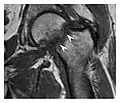

Figure 1: A 56-year-old woman presenting with left knee pain after a fall. (a) Initial anteroposterior radiograph was considered normal, however, subtle cortical disruption of the anterior rim of the medial tibial plateau, medial to the tibial spine, is noted (arrow). (b) Coronal T1-weighted MRI confirms the cortical disruption (arrow) and shows extensive fracture through the proximal tibia. (c) Coronal proton density-weighted image with fat saturation shows extensive edema in the subchondral bone. Note also hypersignal adjacent to the medial collateral ligament corresponding to a grade I sprain (arrowheads).[1]